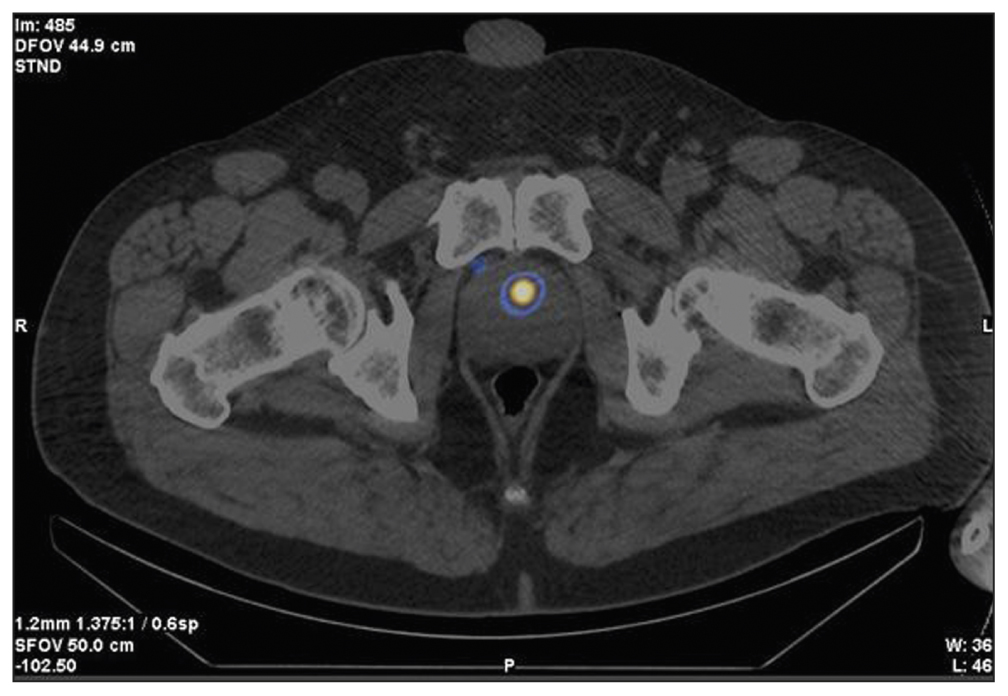

Case report 3

Patient K., 73 years old, was admitted with diffuse prostatic hyperplasia, urinary retention, an epicystostomy, and a 12.7-ng/mL PSA. A multisite biopsy performed under US guide revealed no evidence of malignant development. SPECT/CT data with 99mTc-HYNIC-PSMA are shown in Figure 4. SPECT/CT revealed a 14-mm3 site of RP accumulation in the prostate tissue. A CT-guided targeted biopsy was performed using pararectal access. A morphological diagnosis was adenocarcinoma, Gleason 6 (3 + 3).

Fig. 4. Patient K., 73 years old, SPECT /CT with 99mTc-HYNIC-PSMA, (a) frontal and (b) axial sections: Sites of radiopharmaceutical accumulation in the anterior part of the transition zone in the apex of the right lobe, posterolateral part of the peripheral zone at the level of the base of the left lobe, and posterolateral part of the peripheral zones at the level of the base and middle third of the left lobe of the prostate gland; physiological accumulation of radiopharmaceuticals in the bladder.

On November 28, 2020, CT-guided focal implantation of 125I sources was performed pararectally. Transurethral resection of the intravesical component was performed, and the epicystostomy was removed. The follow-up examination (November 28, 2022) showed a PSA level of 0.13 ng/mL, spontaneous urination, and 15-cm3 residual urine.

In this case, problems were as follows: inability to identify the cause of elevated PSA, a “large” volume of the prostate gland, and epicystostomy. Considering data on RP accumulation patterns and biopsy results, we were unable to successfully solve these problems and perform successful focal brachytherapy using a hybrid diagnostic use of RP CT-guided biopsy.